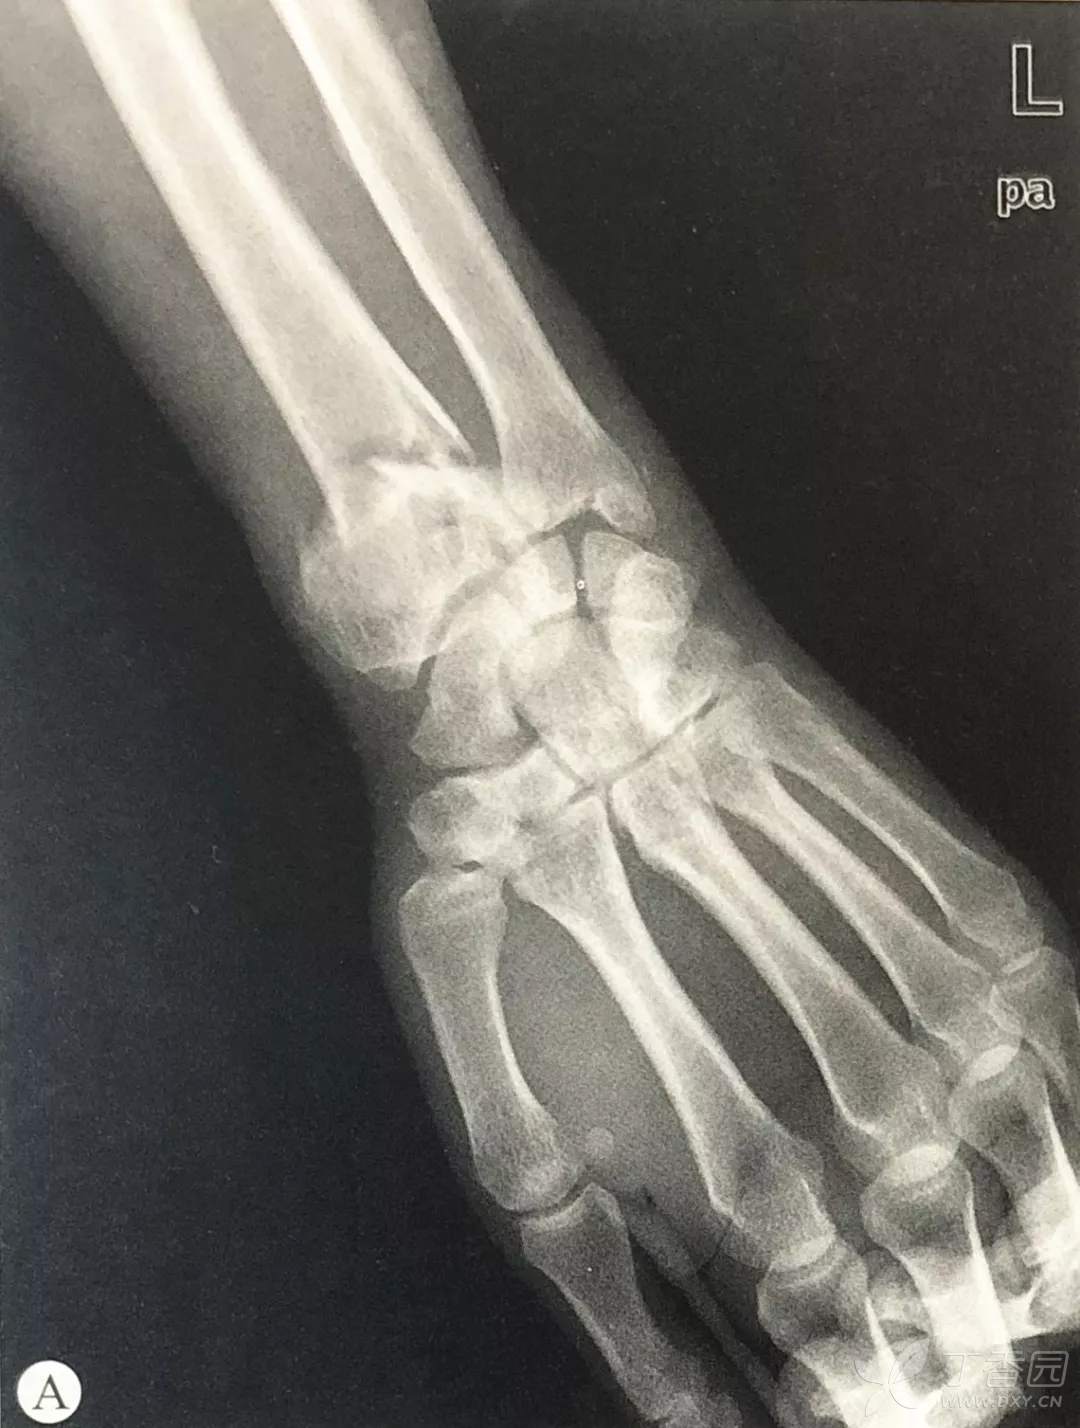

桡骨远端骨折手术技巧:切开复位内固定术

关节内骨折:

根据Melone分型,关节内骨折需要解决桡骨茎突、背侧唇、掌侧唇、冲床死骨以及尺骨远端骨折。